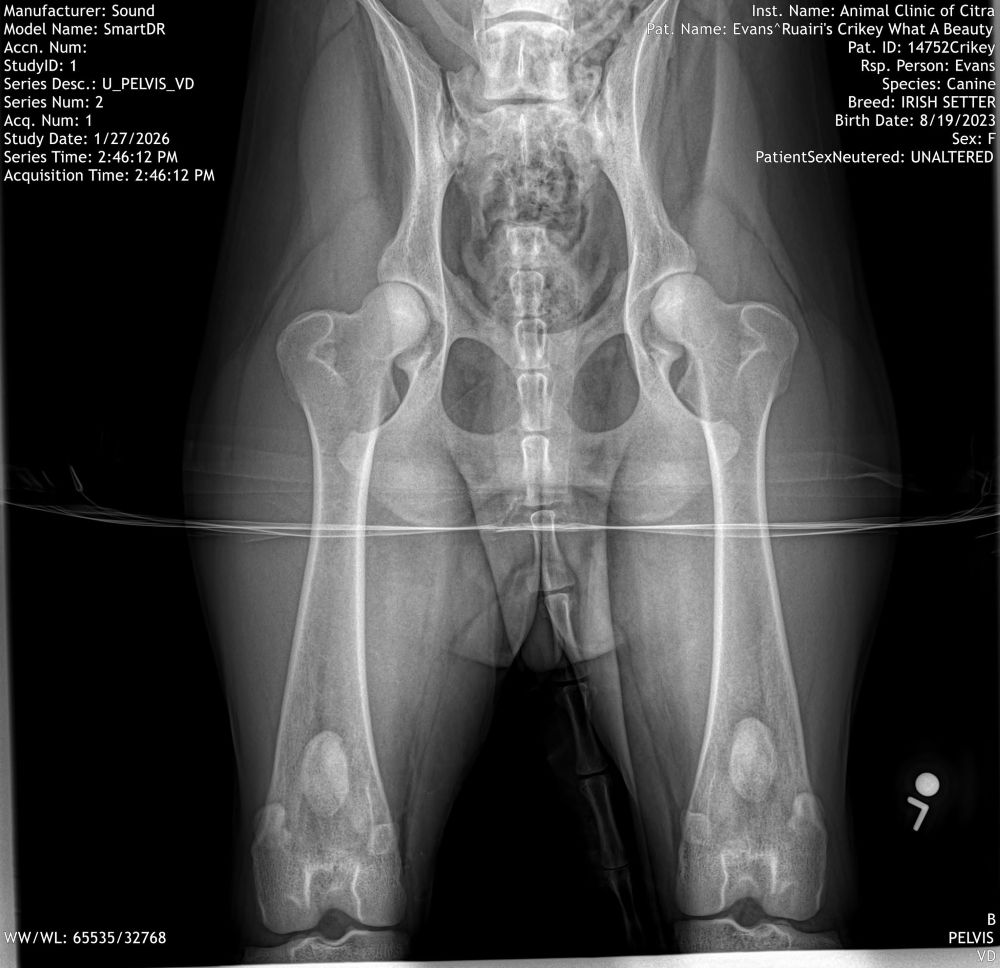

SS42999101 HIPS-GOOD-IR-13414G29F-P-VPI PRA-IR-PRA-872/11F-PI RCD4-IR-P4-412/11F-PI VWD-IR-VWD-129/11F-PI CLAD-IR-CLD-450/11F-PI DM-IR-DM-202/11F-PI GCL-IR-GCL-125/11F-PI THYROID-Normal IR-TH1489/29F-VPI AKC DNA-V10115388 Microchip 900263004477214 CHIC#